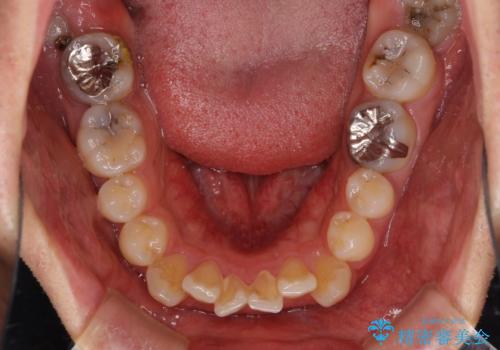

- 口元の突出感を治したいとのことで来院された患者様です。

上下顎ともにIPR(歯と歯の間を削る)と歯列全体の拡大によって口元が引っ込むように設計し、インビザラインにより治療を行うこととしました。

抜歯をして口元を下げなければならないほど出っ歯ではなかったため、少しずつ治療ゴールを変更しながら仕上げていきました。

気になっていた前歯の飛び出した印象は、最終的にはスッキリと引っ込み、大変満足していただきました。